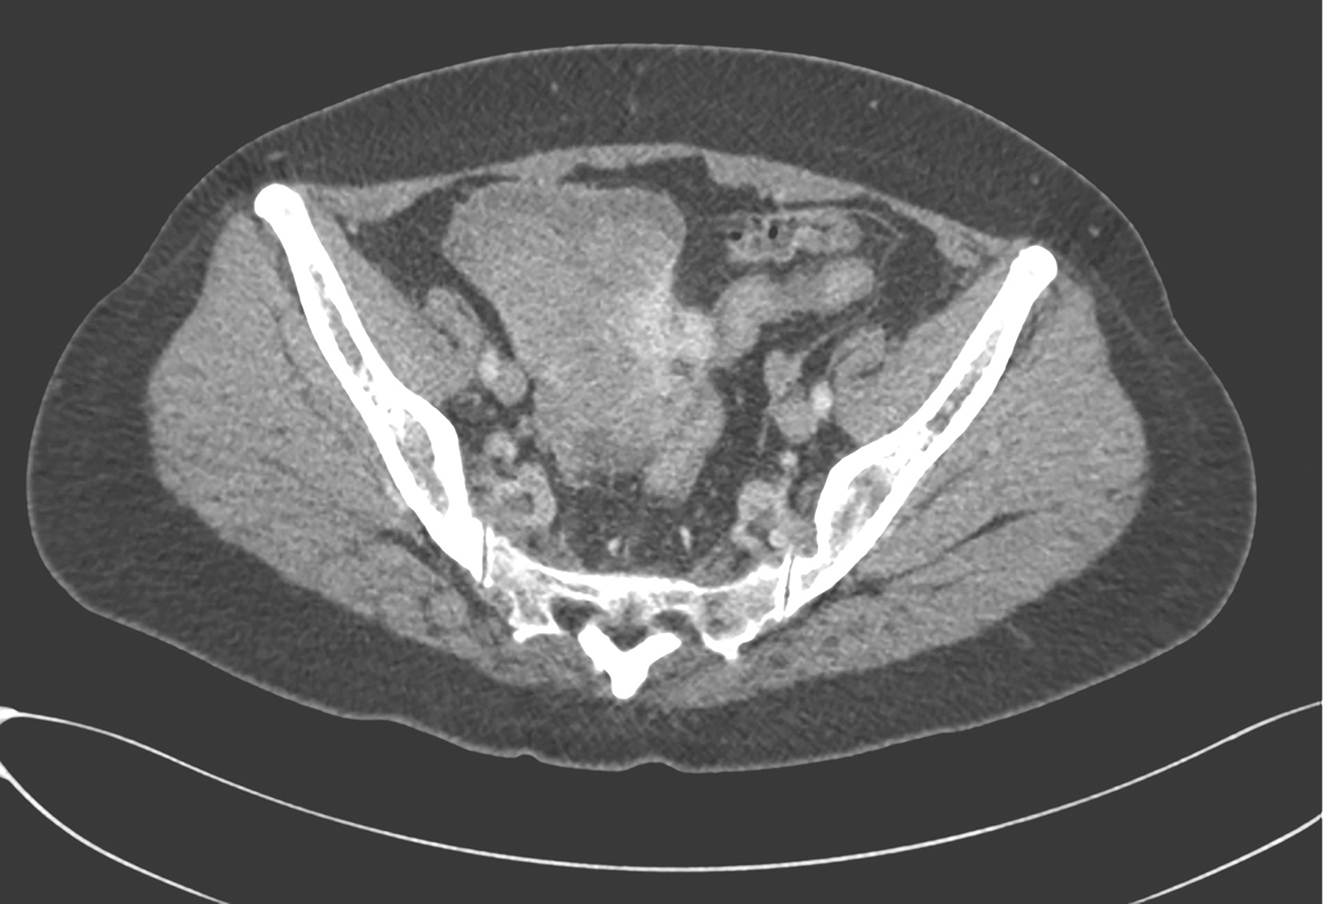

患者开始400mg/d伊马替尼治疗2周后,复查腹部CT见:①左肾中上份见巨大不规则肿块影,最大截面约15cm×10cm,其内密度不均匀,内散在点状钙化灶,增强扫描呈明显不均匀强化,可见粗大引流静脉,肾盂受压积液。肿瘤体积与前无明显变化。②盆腔偏右份见不规则肿块影,最大截面约9cm×9cm,增强扫描呈明显不均匀强化,盆腔肿块较前明显缩小(图3)。再次MDT讨论决定行同期肾脏肿瘤及盆腔肿瘤切除。

图3术前治疗后复查CT示盆腔GIST明显缩小